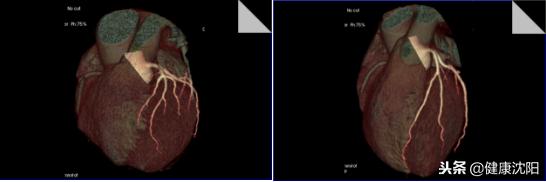

VR三维显示可以直观显示血管的大体形态、解剖,可以对病变进行明确的定位、定性诊断,可以直观地显示血管狭窄、血管瘤、动静脉畸形等病变,还可以间接判断血管壁的病变,进而提供进一步检查的必要性。CTA检查的VR技术实现了无创检查就能了解自己血管形态的目的。

显示冠脉与心脏VR主次重叠图像,可以反映冠脉的心肌供血区域对照